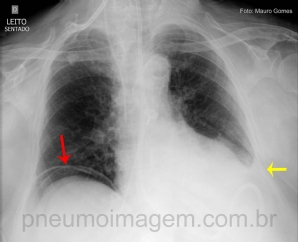

CASO CLÍNICO #40

O que a seta aponta nessa radiografia? Deixe os seus comentários abaixo! ***** What the arrow points in this chest X? Write your comments below.